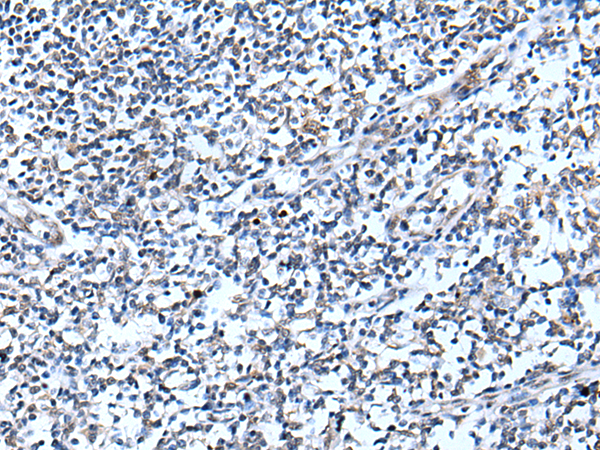

- The image is immunohistochemistry of paraffin-embedded Human tonsil tissue using P12717(CDC34 Antibody) at dilution 1/20. (Original magnification: ×200)

- The image is immunohistochemistry of paraffin-embedded Human colorectal cancer tissue using P12717(CDC34 Antibody) at dilution 1/20. (Original magnification: ×200)